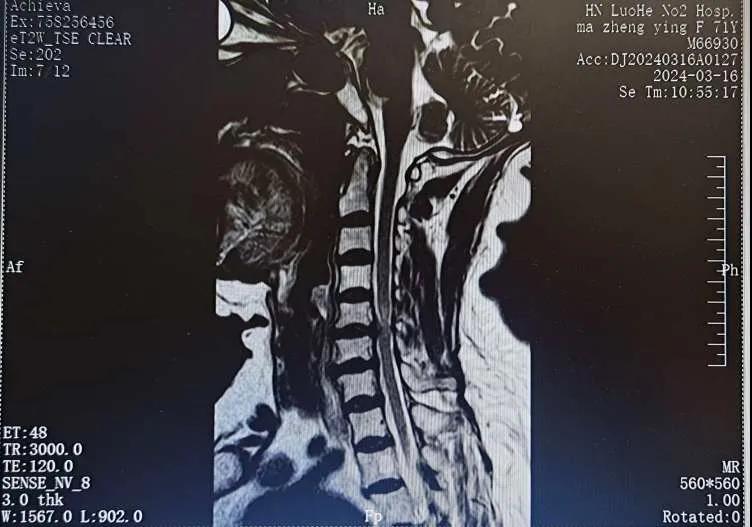

近日,70歲的馬阿姨,因摔傷后出現(xiàn)持續(xù)性頸部疼痛伴右側(cè)肢體無(wú)力、麻痛,影響日常生活。于是來(lái)到市二院神經(jīng)外科就診,經(jīng)檢查發(fā)現(xiàn):頸椎MR示:頸3/4、4/5、5/6、6/7椎間盤變性突出(中央型)并繼發(fā)性椎管變窄,頸椎退行性改變,頸5椎體水平頸髓水腫。神經(jīng)外科副主任劉沛濤根據(jù)患者癥狀、體征、影像學(xué)三者結(jié)合診斷為“脊髓型頸椎病”,考慮到患者癥狀逐漸加重、保守治療效果不佳等情況,建議盡快手術(shù)治療。

經(jīng)過(guò)縝密的術(shù)前準(zhǔn)備和手術(shù)計(jì)劃,在鄭大一附院神經(jīng)外科張風(fēng)江教授的指導(dǎo)下,神經(jīng)外科團(tuán)隊(duì)順利為患者實(shí)施“顯微鏡下頸椎前路C5/C6椎間盤切除椎間融合+內(nèi)固定術(shù)”,手術(shù)時(shí)間不到1小時(shí)。術(shù)后患者恢復(fù)情況良好。